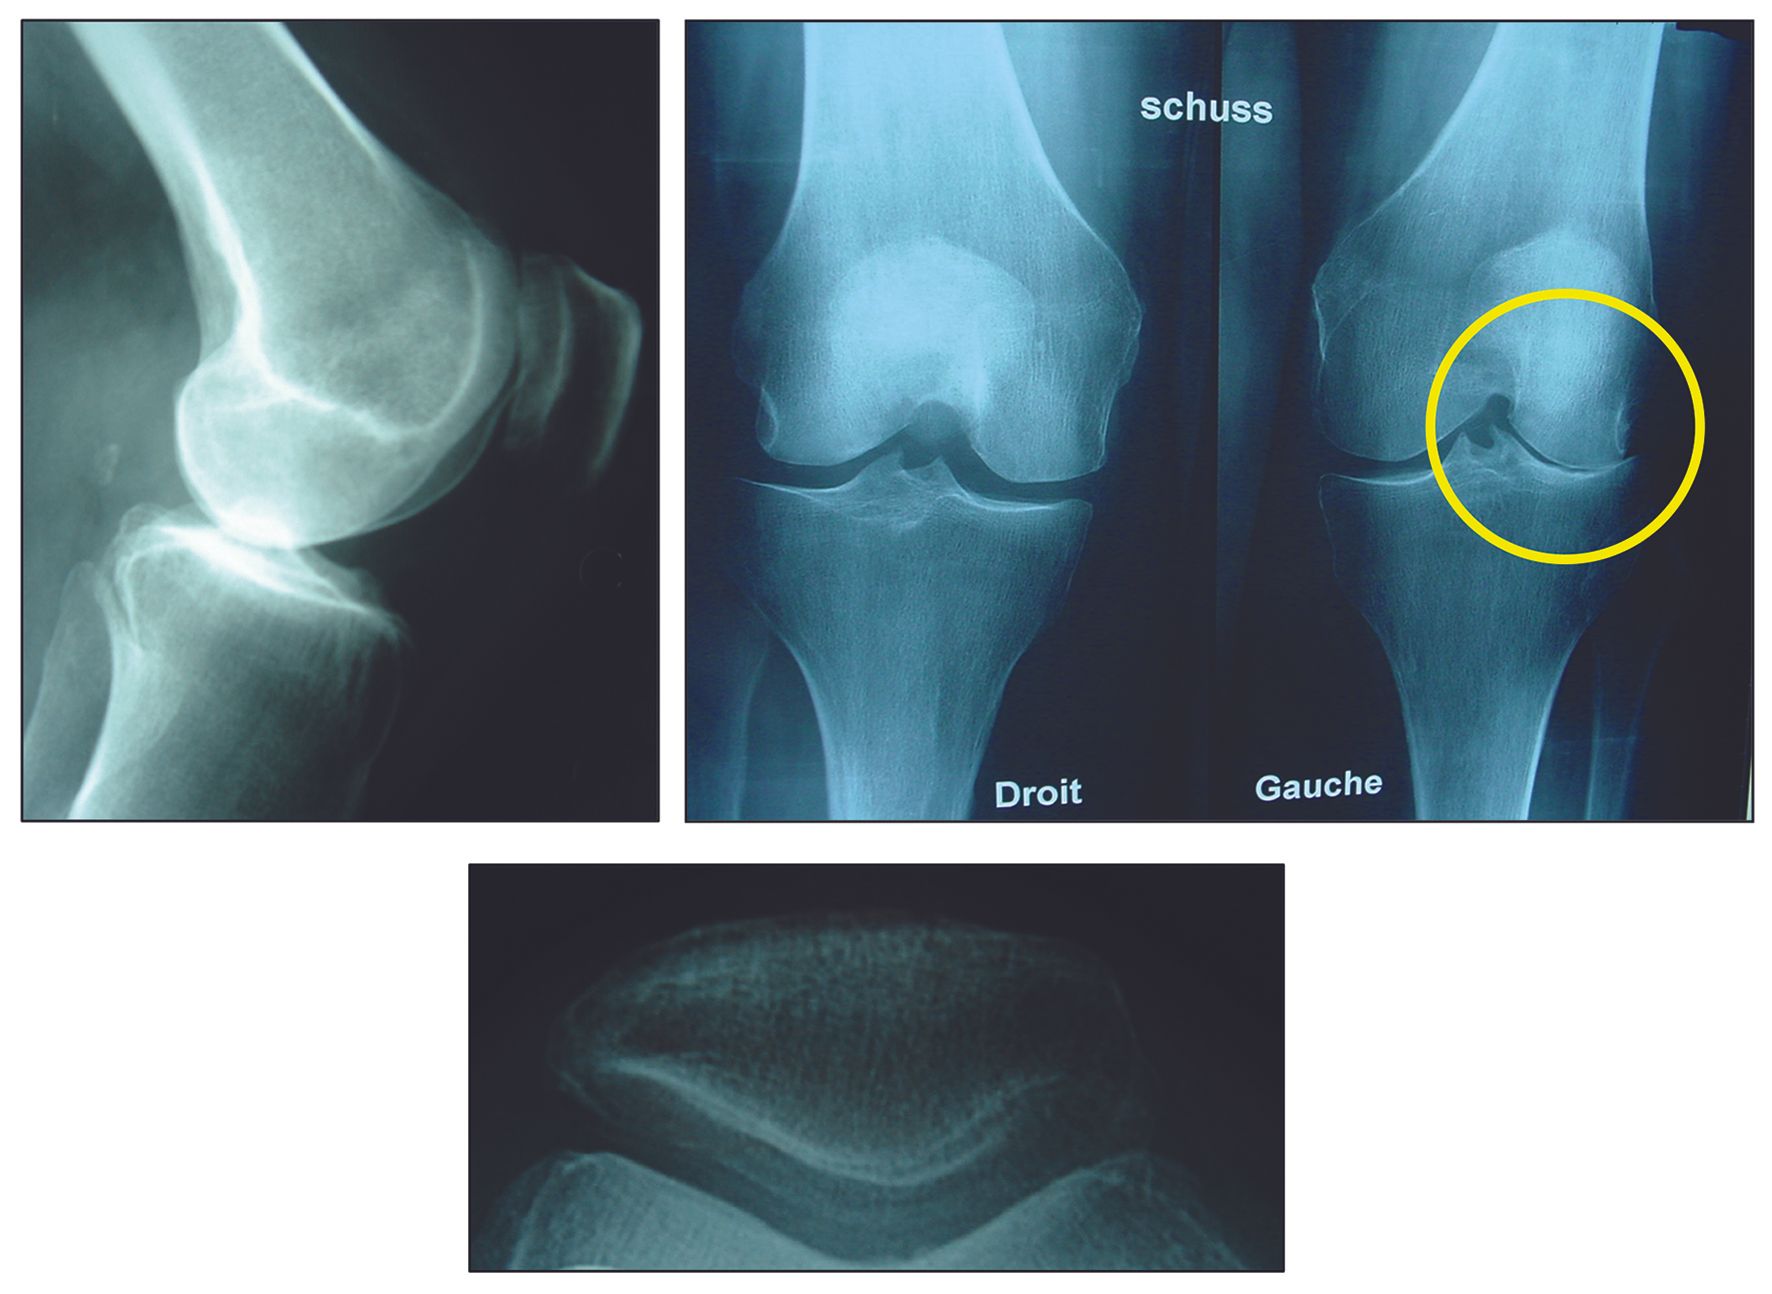

The accompanying articles address key areas in joint preservation and reconstruction. Lateral unicompartmental knee arthroplasty and medial unicompartmental knee arthroplasty are examined with respect to patient selection, procedural indications, and technical precision necessary to ensure durable outcomes. A dedicated contribution on hip arthroscopy on the orthopaedic table outlines technique optimization and complication avoidance. Finally, a pictorial and systematic approach to varus deformity provides a structured framework for deformity assessment and surgical planning.